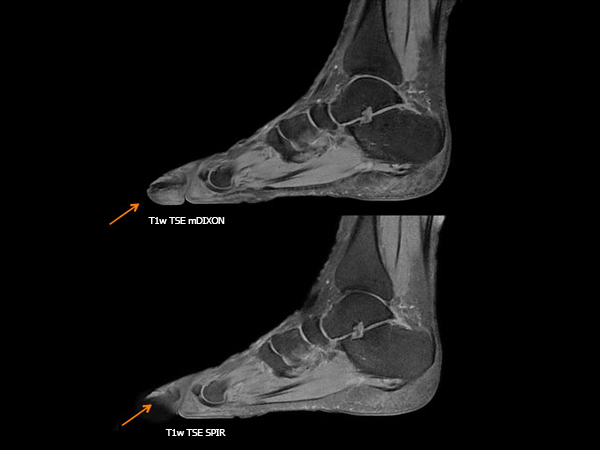

Orthopedic imaging with mDIXON XD TSE